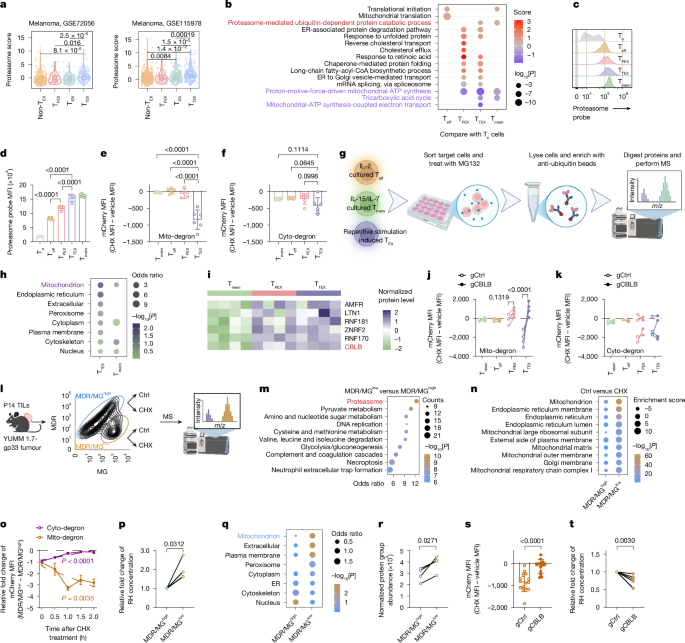

Proteasome-guided haem signalling axis contributes to T cell exhaustion - Nature

Nature, Published online: 18 March 2026; doi:10.1038/s41586-026-10250-yExhausted CD8+ T cells increase proteasome activity due to the accumulation of depolar...